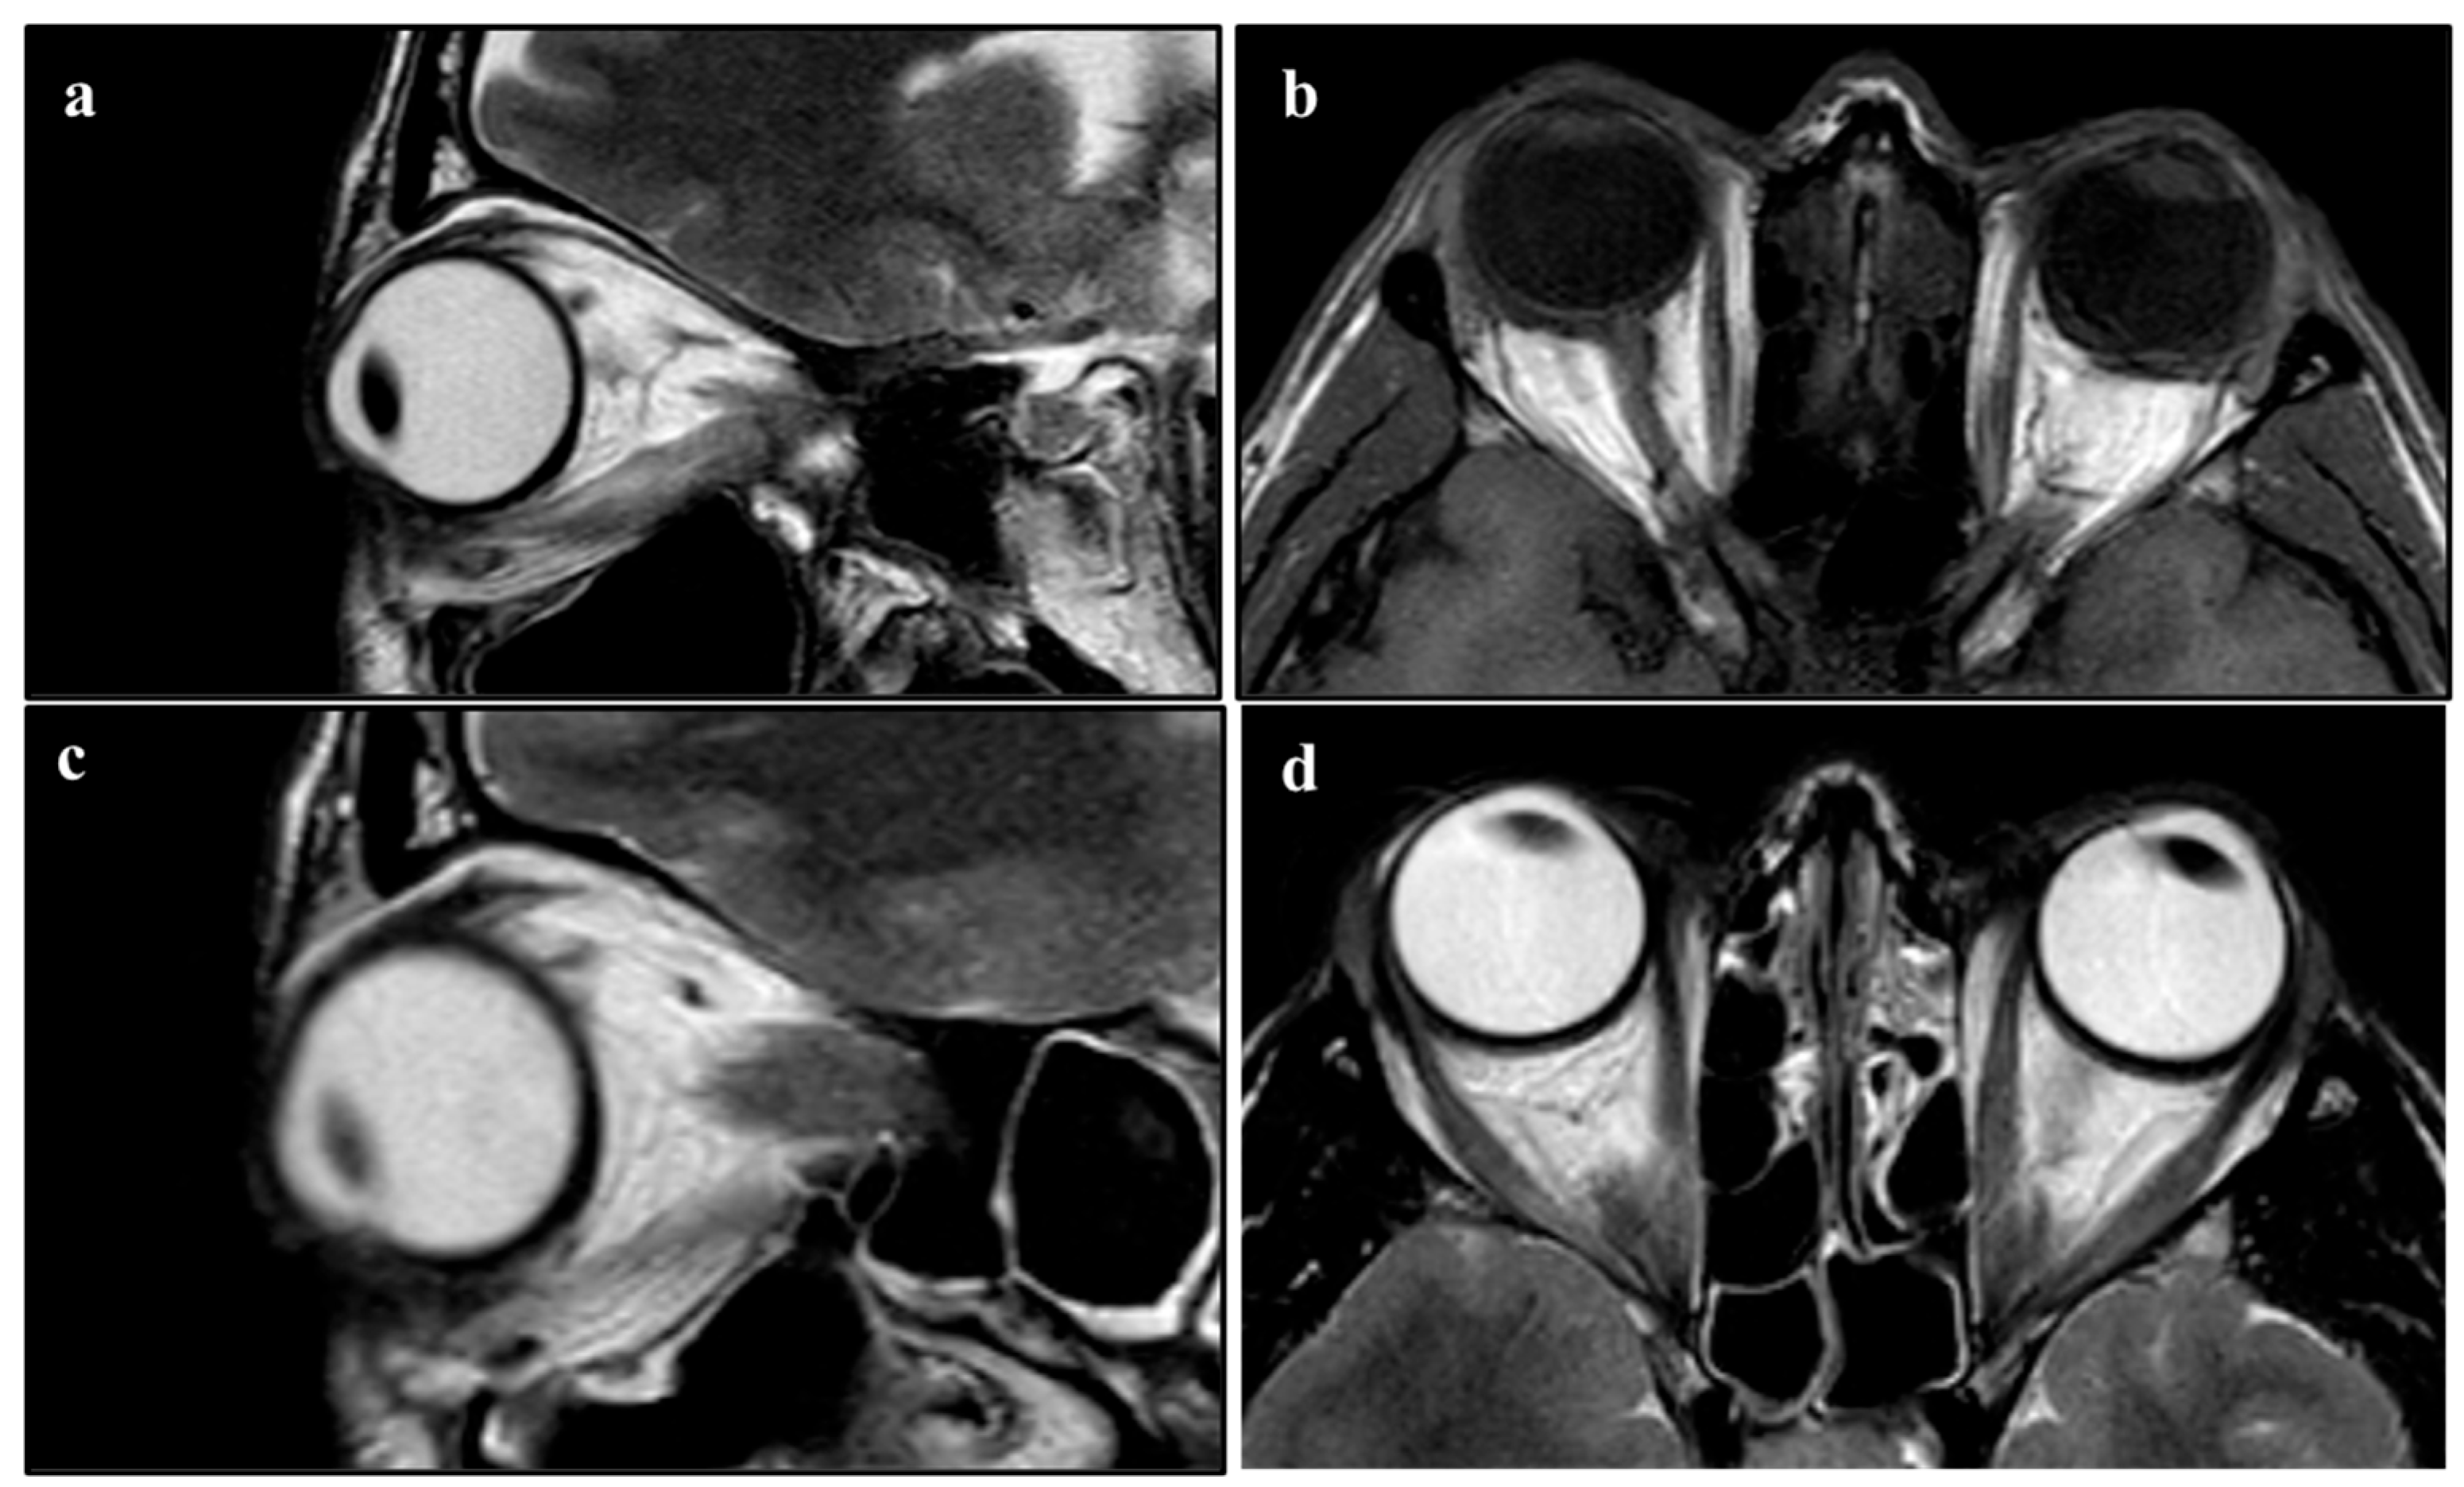

| Joseph A. et al. (2018) [24] | Book chapter | “…Eyelid retraction, lid lag on downgaze and lagophthalmos, and decreased convergence may be found in patients with thyroid-related orbitopathy. Blepharoplasty should be reserved for patients with quiescent disease and undertaken after any proptosis, motility dysfunction, and eyelid retraction have stabilized for 6 months to 1 year or have been definitively treated. In patients with suspected thyroid eye disease, referral to an endocrinologist or internist may be necessary for appropriate systemic workup, including serum thyroid hormone levels (triiodothyronine [T3], levorotatory thyroxine [T4], thyroid stimulating hormone [TSH]). Orbital computed tomography may demonstrate enlargement of the extraocular muscles and increased orbital fat when systemic signs are completely lacking early in the course of the disease…” |

| Kwitko G.M. et al. (2021) [28] | Review | “...Most contraindications for ptosis surgery revolve around the exposure of the cornea. Conditions like thyroid orbitopathy, progressive external ophthalmoplegia, or loss of Bell’s phenomenon can make patients more prone to exposure keratopathy after ptosis surgery: a more conservative approach is needed in these patients…CT scan of the orbits should be obtained if an orbital process such as thyroid orbitopathy or an orbital tumor is suspected. Slit lamp evaluation is essential to detect corneal erosions or dry eye…” |